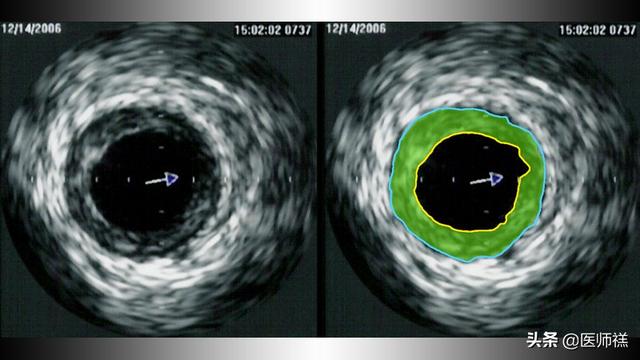

いわゆる心臓への血液供給不足は、臨床的にはこうも呼ばれる。心筋虚血これは通常、「与える」という意味である。心臓に血液を供給する冠動脈と静脈の一部または全部が閉塞すること。下の写真のように。

まず説明させてほしいことがある。冠動脈の概念私たちが話しているのは冠動脈、静脈心臓の筋肉細胞に血液を供給する役割を担っている。クラウン同じ血管である。例えば冠動脈は、人体では大動脈の付け根から発生し、左右の枝に分かれて心臓の表面に広がって血液を供給する。心臓への血液供給における冠動脈の利点のひとつは、以下の通りである:冠動脈は血液に対する抵抗が少ない。心筋細胞に継続的に栄養を供給する方法として、冠動脈抵抗全体の5%未満である。そして、これらの血管の部分的または完全な閉塞その結果、心臓に十分な血液が供給されなくなる。